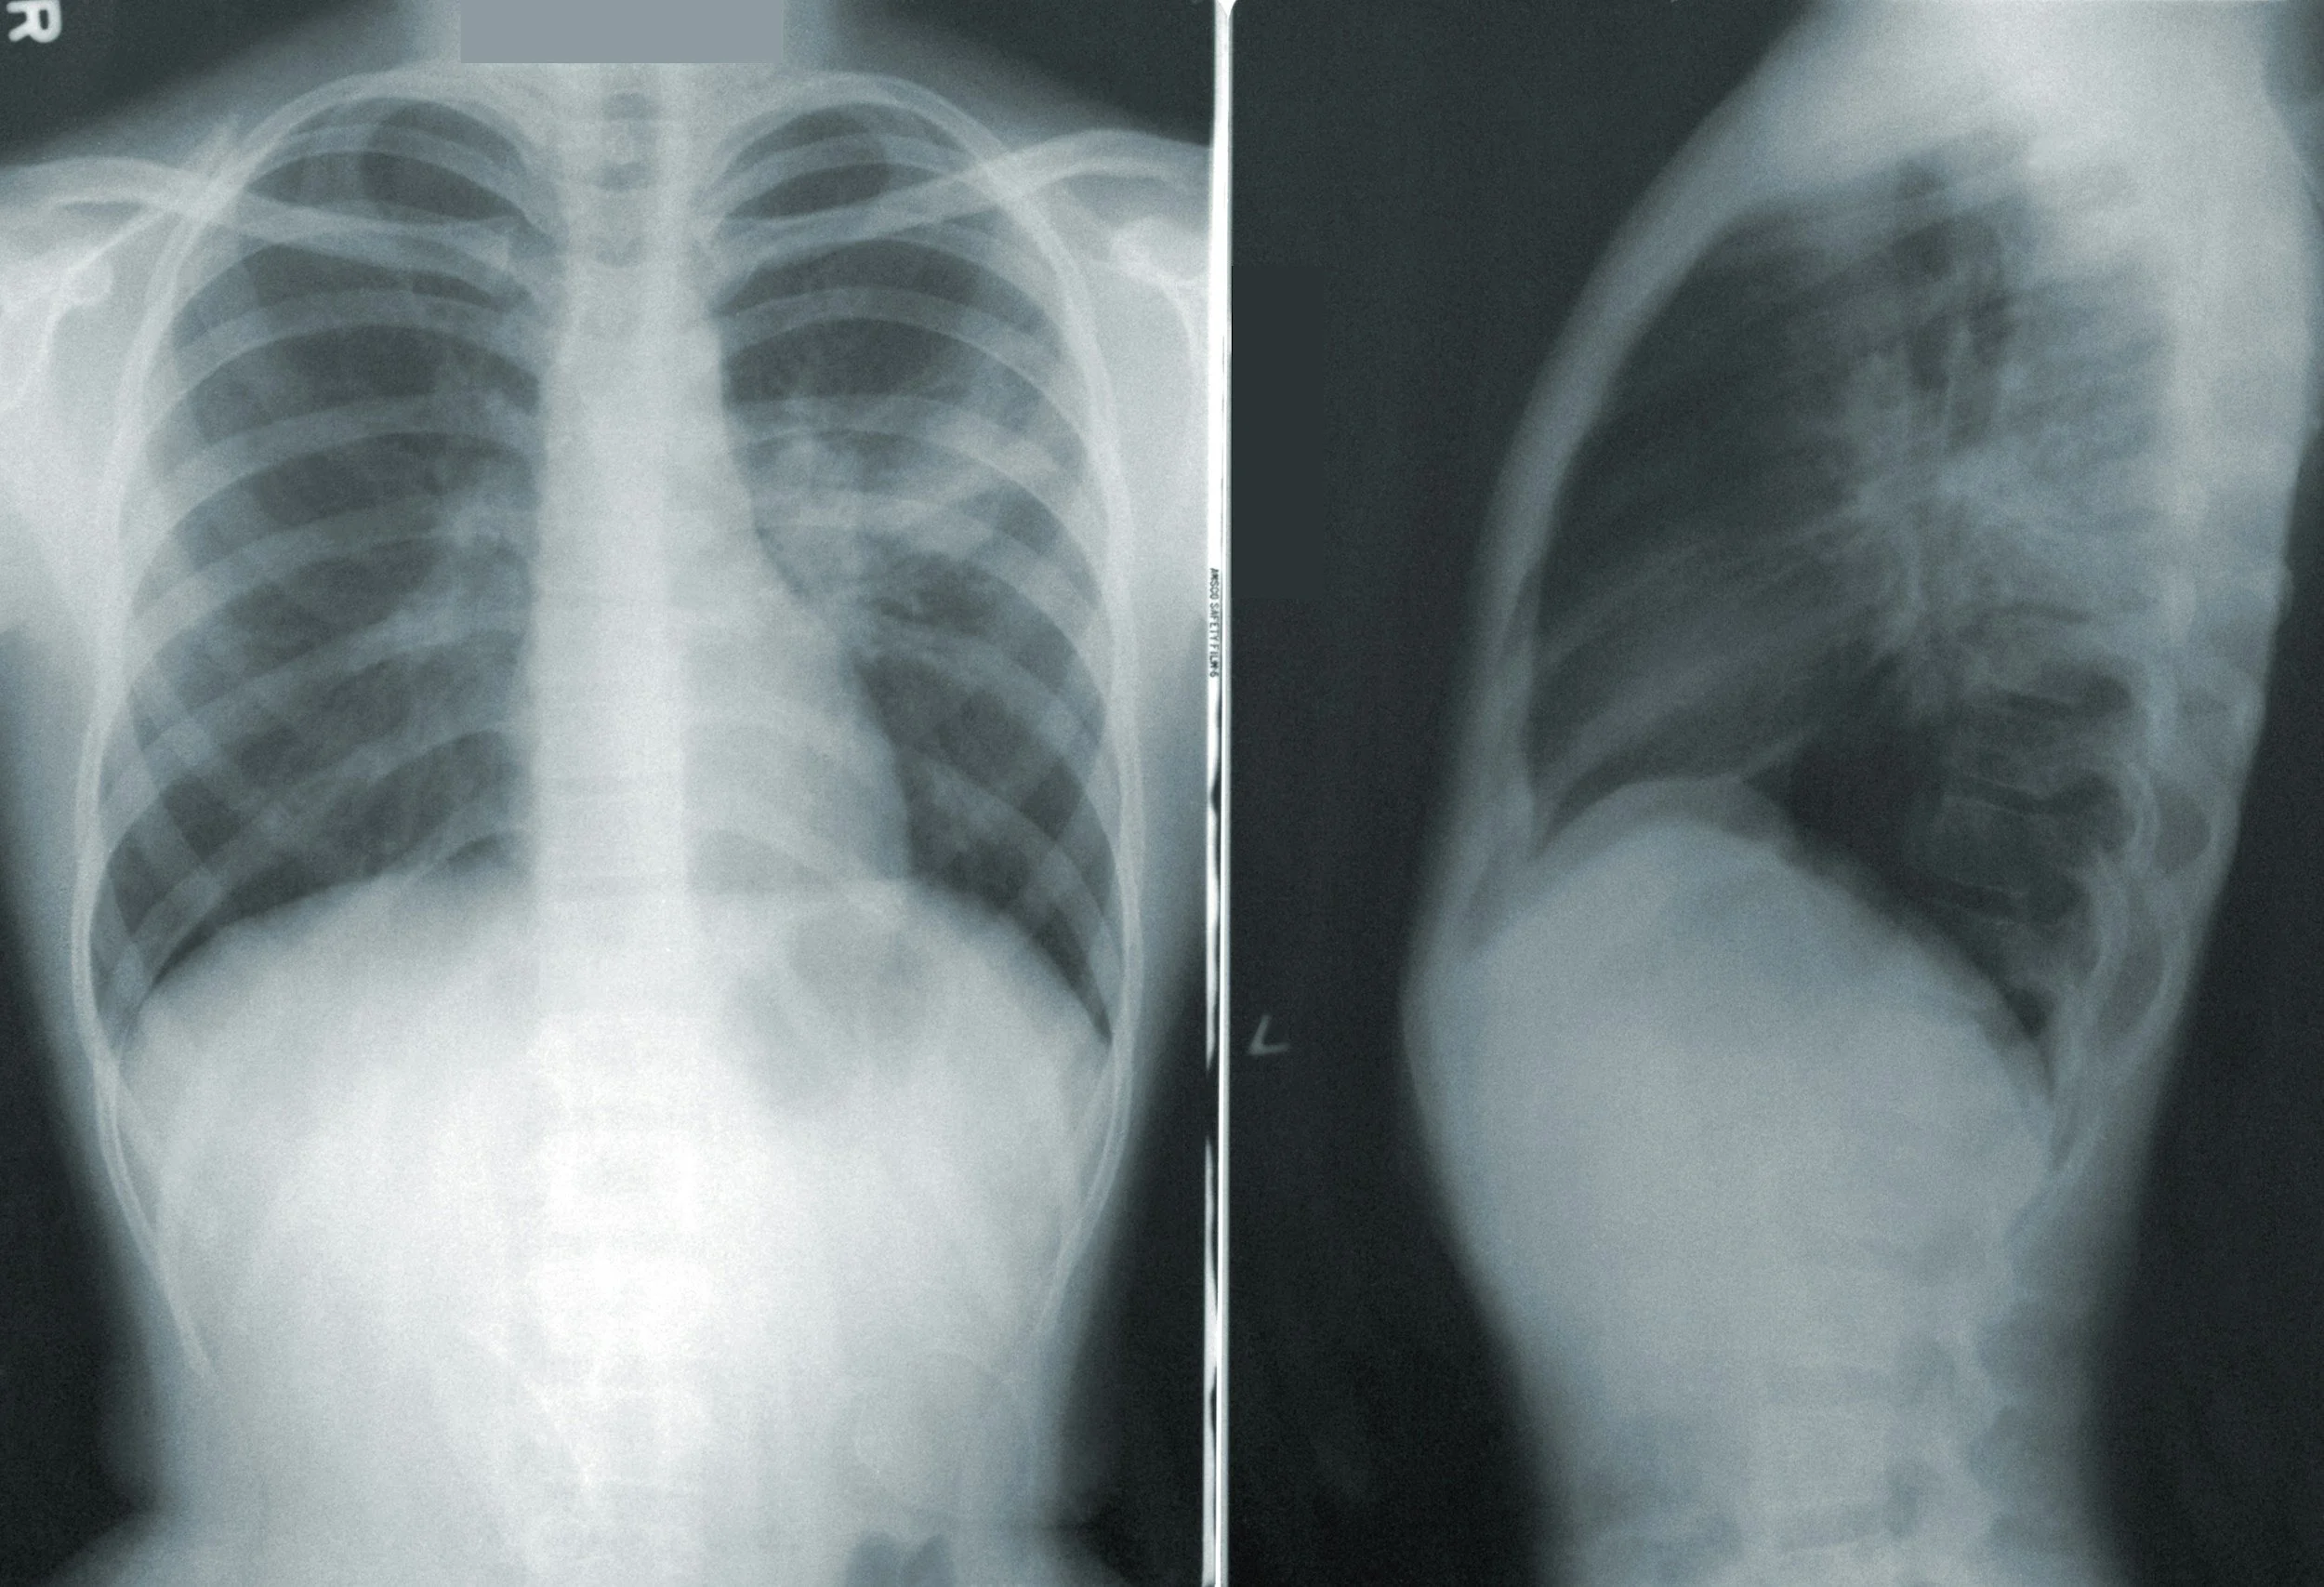

Research reviewing scoliosis patients found that spinal radiographs remain the gold standard for diagnosing and monitoring spinal curvature, because they allow physicians to directly measure the Cobb angle, evaluate vertebral rotation, and assess structural changes in the spine.

X-rays allow us to measure spinal curvature using the Cobb angle and monitor progression over time.